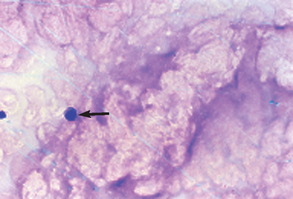

Once designated as inflammatory, the cells must also be evaluated for evidence of degeneration and presence of microorganisms. Nuclear changes that may be found in inflammatory cells (e.g., neutrophils) include karyolysis, karyorrhexis, and pyknosis, with karyolysis having the greatest significance. Pyknosis represents slow cell death (aging) and refers to a small, condensed, dark nucleus that may fragment (karyorrhexis). Karyolysis represents rapid cell death, as in some septic (bacterial) inflammatory reactions, and appears as a swollen, ragged nucleus without an intact nuclear membrane and with reduced staining intensity. Cells should also be evaluated for the presence of bacteria. Inflammatory cells that contain phagocytized microorganisms are referred to as septic (Fig. 9-31). Additional phagocytized material may include erythrocytes, parasites, and fungal organisms (Fig. 9-32).

Epithelial cell tumors are also referred to as carcinoma or adenocarcinoma. The samples tend to be highly cellular and often exfoliate in clumps or sheets (Fig. 9-33). Mesenchymal cell tumors are also referred to as sarcoma and are usually less cellular. The cells tend to exfoliate singly or in wispy spindles (Fig. 9-34). Discrete round cell tumors exfoliate very well but are usually not in clumps or clusters. Round cell tumors include histiocytoma, lymphoma, mast cell tumors, plasma cell tumors, transmissible venereal tumors, and melanoma. Histiocytoma and transmissible venereal tumors appear somewhat similar except that histiocytoma is not usually highly cellular (Fig. 9-35). Plasma cell tumors can be recognized by the presence of large numbers of cells with an eccentri-cally located nucleus and prominent perinuclear clear zone (Fig. 9-36). Mast cells can be recognized by their prominent purple/black granules (Fig. 9-37). Melanoma is characterized by cells with prominent dark black granules (Fig. 9-38). Occasionally, cells from poorly differentiated tumors may contain few or no granules (amelanotic melanoma).